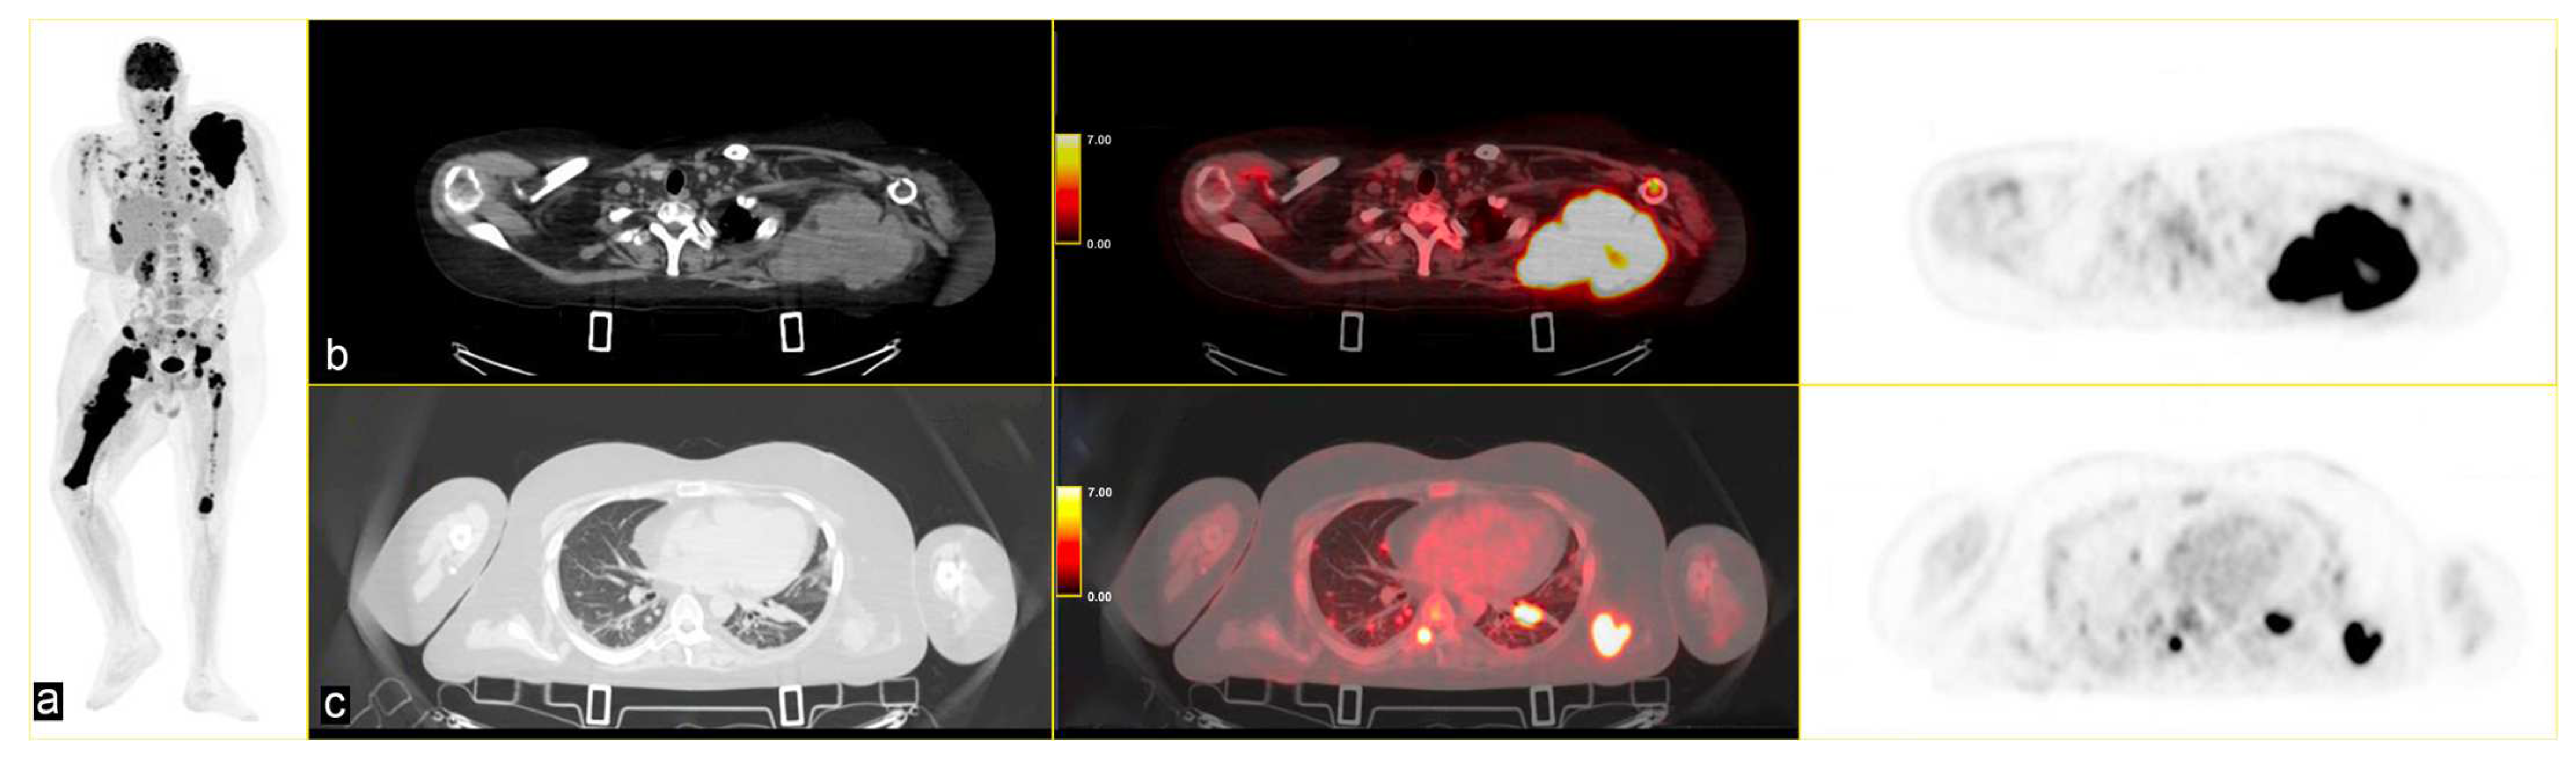

The patient continued third-line antineoplastic treatment with Gemcitabine (750 mg/mq) and Taxotere (75 mg/mq) for three cycles until disease progression. Fourth-line treatment with trabectedin (1.25 mg/m2) followed, reporting bone marrow and liver toxicity. The last PET scan, performed in May 2024, showed an increased uptake of FDG in several pseudonodular lesions in both lungs at the pleuro-parenchymal level (SUVmax 25.3 vs. 10.9), and in the left axillary lymphnodes (SUVmax 17.4 vs. 6.1). A new, unknown area of glucose hypermetabolism was depicted in the body of the pancreas (SUVmax 4.0), highly suspicious for metastasis. The lesion of the right femur extended to the whole bone, with other secondary lesions in the skull [Figure 4].

Figure 4.

(a) MIP PET/CT showing significant disease progression; (b) volumetric and metabolic increase of the lesion in the left scapula (SUVmax 35); and (c) multiple lesions in the upper lobes of both lungs (SUVmax 25.3) on (b,c) strips CT on the left, PET/CT fused images the middle and PET images on the right.